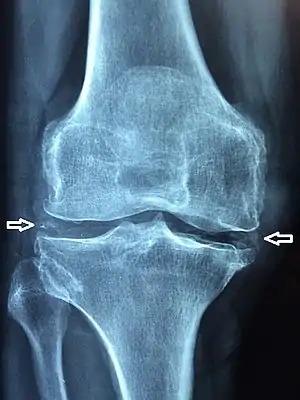

軟骨鈣質沈積病(英語:)又稱為軟骨鈣化是指透明軟骨和/或纖維軟骨的鈣化(鈣鹽沈積)[1]。可以在放射線攝影術或 X 光檢查時發現。

| 膝關節X 光檢查發現軟骨鈣質沈積 | |

軟骨鈣質沈積病能以X 光、X射線計算機斷層成像(電腦斷層掃瞄,CT scan)、核磁共振成像(MRI)、醫學超聲檢查和核醫學確診[1]。CT 和 MRI 掃瞄可以看到鈣化腫塊(通常在黃韌帶或關節囊內),然而,X 光檢查才是這個問題最佳診斷工具[1]。超音波檢查時,透明軟骨內可能會出現高超音波顯影且無超音波陰影(acoustic shadow)的病兆[7]。與多數情況一樣,軟骨鈣化與其它疾病(如:僵直性脊椎炎和痛風)的臨床表現可能很相似,且不易鑑別[1]。